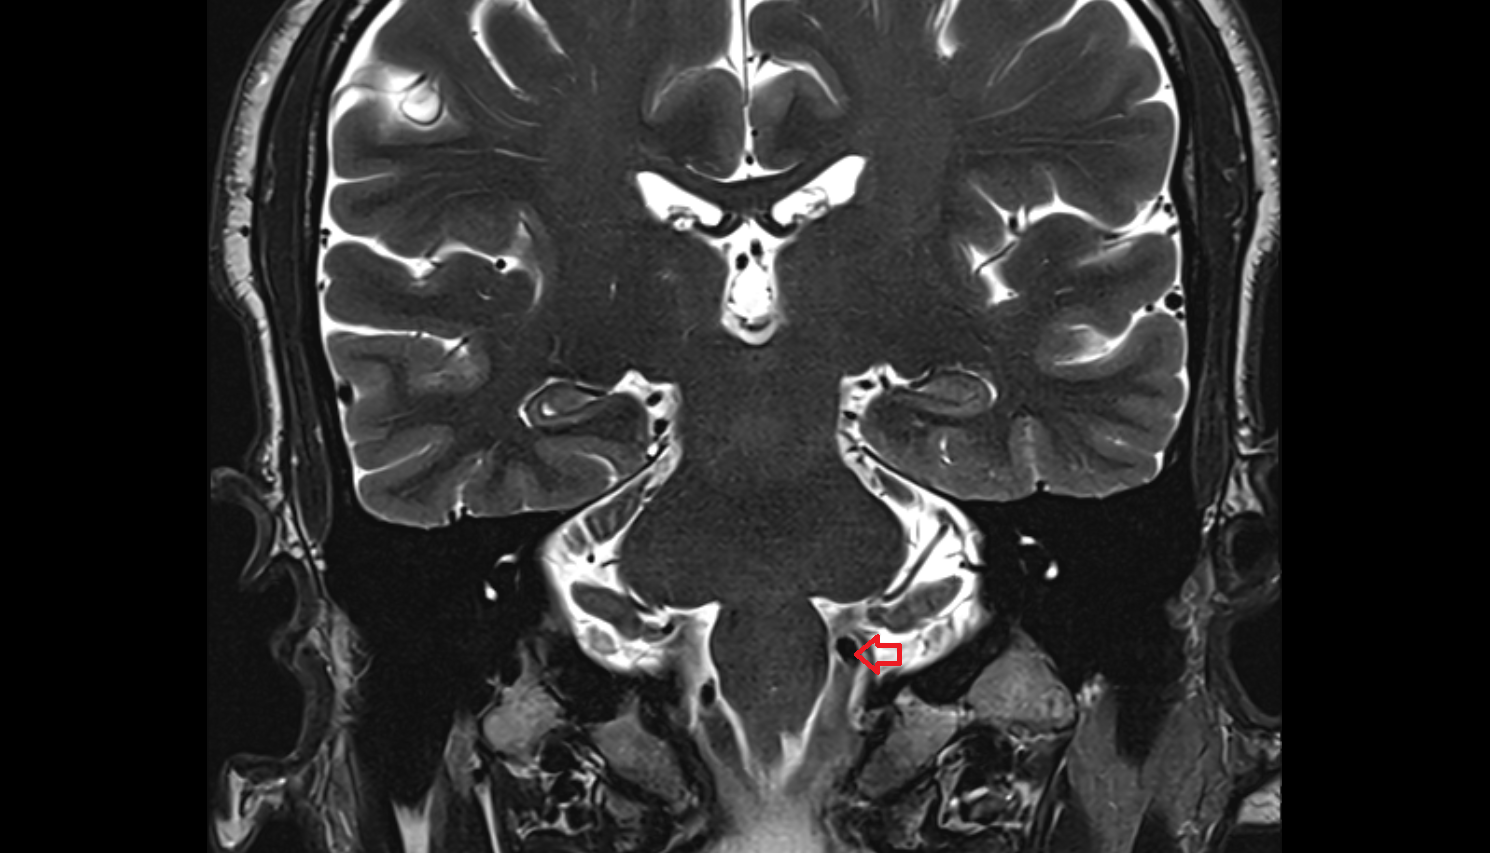

- Occipital condyle

- Atlantooccipital joint

- Cisterna magna